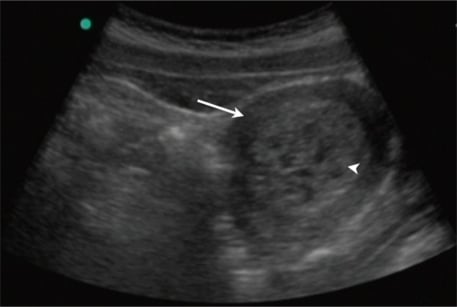

Fig 2 - A transabdominal ultrasound of the pelvis revealing a uterus (arrow) with multiple cystic areas within an enlarged echogenic endometrial cavity (arrowhead). This is consistent with a molar pregnancy.

A transabdominal ultrasound of the pelvis revealing a uterus (arrow) with multiple cystic areas within an enlarged echogenic endometrial cavity (arrowhead). This is consistent with a molar pregnancy.